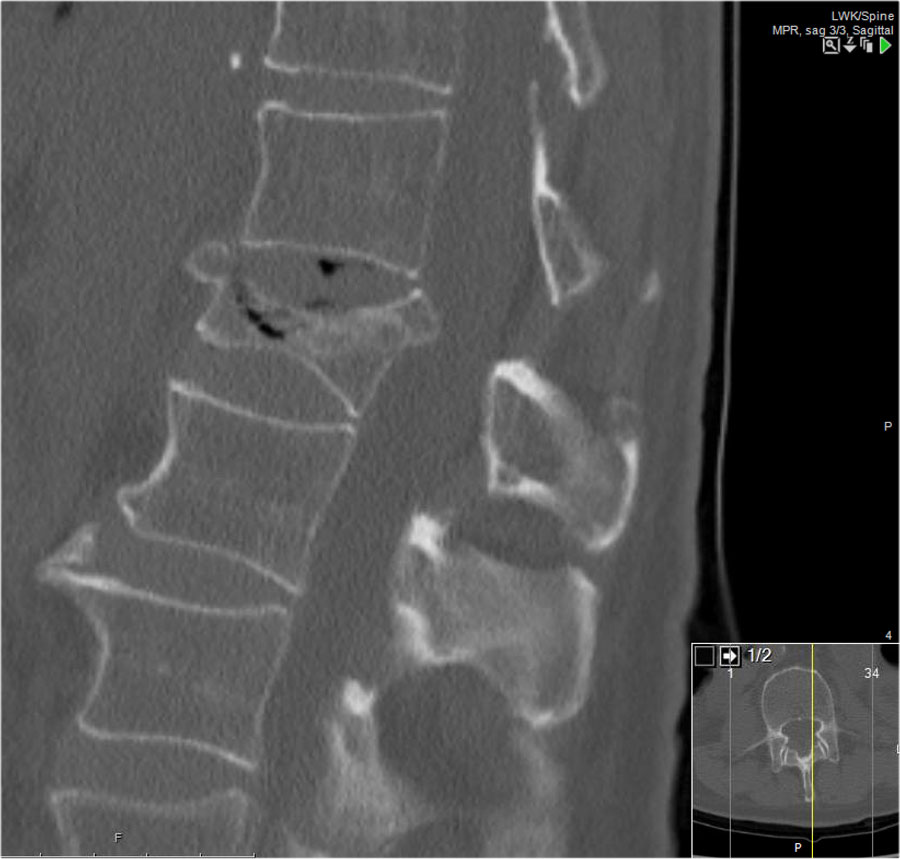

Mảnh xương góc sau trên thân đốt sống bị đẩy lùi ra sau (Retropulsion)

Hiện tượng mảnh xương bị đẩy lùi ra sau là đặc điểm điển hình của gãy vỡ, phân biệt rõ ràng với gãy nén đơn thuần.

Cuộn qua các hình ảnh.